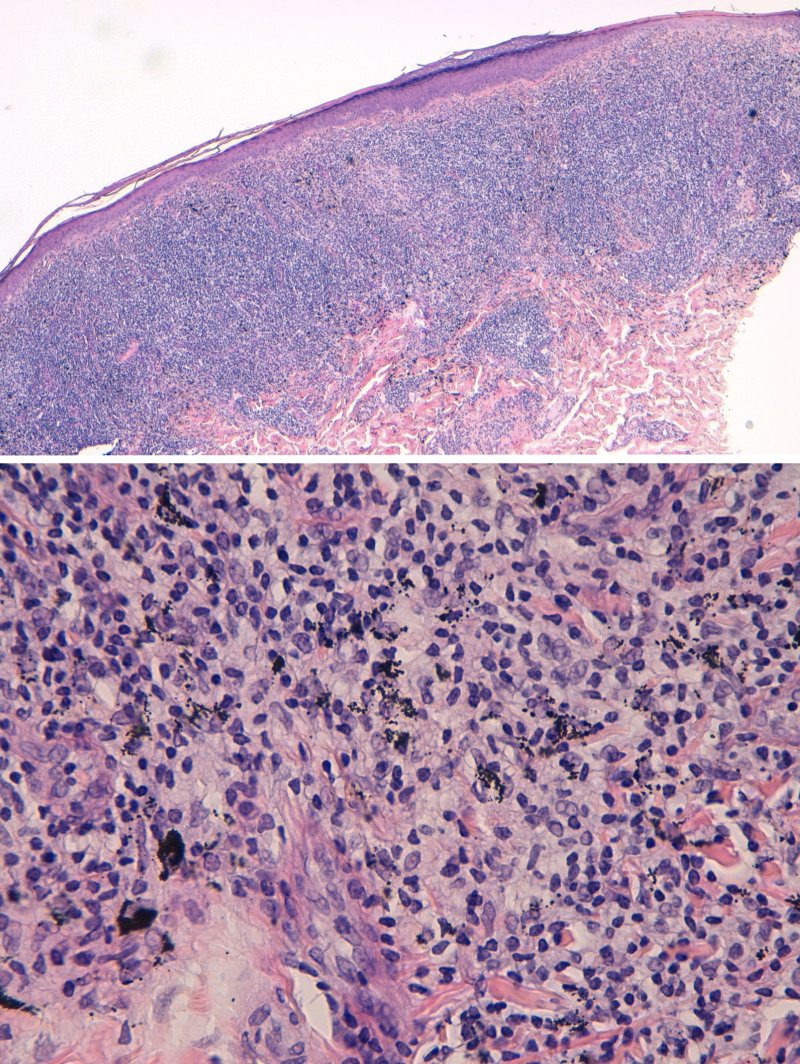

一名43岁男性,在其腿部纹身的红色染料区域出现瘙痒性结节性病变,在应用纹身4周后出现。使用标准系列进行斑贴测试,纹身师使用的墨水是半开放的。测试发现对含有偶氮有机染料(色素红170)、二酮吡咯(色素红254)和酞菁铜(色素蓝15)的2种油墨有敏化作用。组织病理学结果提示假淋巴反应,可能是由t细胞对红色色素过敏引起的。虽然贴片测试在评估纹身反应方面的效用并不是双方都同意的,但它在识别冒犯墨水方面是有用的,有助于指导未来纹身的选择,防止复发。包括疑似墨水的斑贴试验不应被排除在诊断检查之外。

A 43-year-old male presented with pruritic nodular lesions in the red dye area of his leg tattoo, which developed 4 weeks after its application. Patch tests were performed using a standard series, and the inks used by the tattooist were tested semi-open. Tests identified a sensitization to 2 inks containing an azo-organic dye (Pigment Red 170), diketopyrrolopyrrole (Pigment Red 254), and copper phthalocyanine (Pigment Blue 15). Histopathological findings suggested a pseudolymphoid reaction, likely driven by T-cell hypersensitivity to the red pigments. Although the utility of patch testing in the assessment of tattoo reactions is not consensual, it can be useful in identifying the offending inks, helping to guide future tattoo choices and prevent recurrences. Patch testing including the suspected ink should not be disregarded from the diagnostic workup.